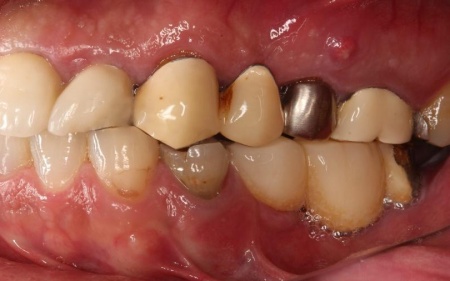

「30代から歯科医院に通っていたが、歯が痛むときだけしか受診しなかったせいか、歯が折れて欠損部が増え、噛みにくくなってしまった。また、今までいくつかの歯科医院を受診したが解決が難しく、こちらを受診した」とご相談いただきました。

拝見したところ、右上奥歯4本が欠損しており、その影響で全体の噛み合わせのバランスが崩れていました。

加えて、噛んだときに上下の歯の中心がずれており、顔貌のゆがみにもつながっています。

欠損部が多い状態が長期間続いたことで噛み合わせが低く、新しい歯を入れるための高さも不足していました。

また、右上前歯も1本欠損しており、両隣の歯を土台として橋を渡すように連結した被せ物「ブリッジ」が装着されていましたが、土台となっている右上前歯2本(中切歯、犬歯)が割れており、温存が難しい状態です。

さらに、劣化してうまく適合していない被せ物、詰め物、既存のインプラントが複数見られ、これらも噛み合わせを乱す原因となっていました。

加えて全体的に歯周病も進行しており、骨が溶けている部分も確認できます。